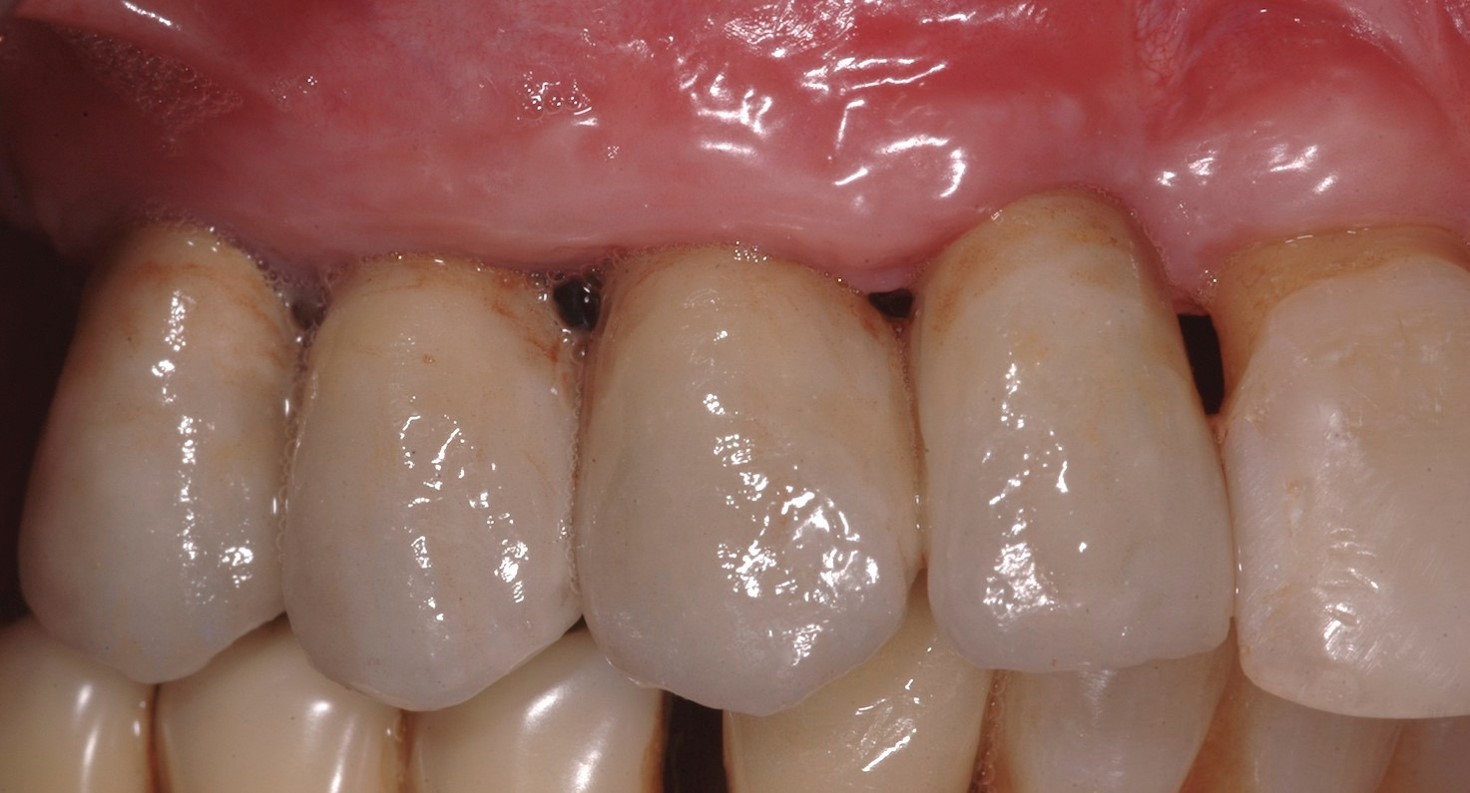

Fig 2. Preoperative view of a female patient who presented with a large defect.

Figure 2